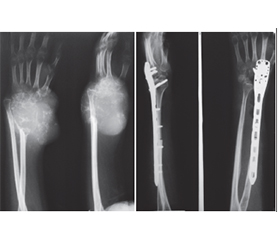

Актуальність. Гігантоклітинна пухлина (ГКП) дистального відділу променевої кістки є доброякісною, місцевоагресивною пухлиною, яка характеризується частими рецидивами та має певний метастатичний потенціал. Внутрішньокісткова або сегментарна резекція дистального відділу променевої кістки з ГКП створює дефект у дистальному відділі променевої кістки. Основними хірургічними методиками реконструкції такого дефекту є застосування спонгіозних ало-/автотрансплантатів, штучних матеріалів, поліметилметакрилату, васкуляризованих і неваскуляризованих кісткових автотрансплантатів, кістково-суглобових алотрансплантатів та індивідуальних ендопротезів. Ми проводили оцінку онкологічних, хірургічних і функціональних результатів при ГКП дистального відділу променевої кістки з урахуванням різних методик хірургічних втручань і реконструкцій. Мета: хірургічне видалення ГКП дистального відділу променевої кістки, зниження ймовірності рецидиву пухлини та збереження функції променево-зап’ясткового суглоба. Матеріали та методи. Проведено хірургічне лікування 21 хворого з ГКП дистального відділу променевої кістки. Середній вік хворих становив 28,7 року (діапазон від 18 до 39 років). Проліковано 8 (38,1 %) пацієнтів із ГКП II/III ступеня (за Кампаначчі) дистального відділу променевої кістки, після резекції дистального сегмента променевої кістки з пухлиною та реконструкції дефекту кістки за допомогою неваскуляризованого малогомілкового автотрансплантата проксимального відділу малогомілкової кістки, фіксованого за допомогою пластини або серкляжів до залишку променевої кістки. 7 (33,3 %) пацієнтам із ГКП I ступеня (за Кампаначчі) проведена внутрішньокісткова резекція дистального відділу променевої кістки з пухлиною та пластика дефекту кістки матеріалом на основі біоактивного скла (біокомпозитом) або спонгіозна автопластика. 1 (4,8 %) пацієнту з ГКП II ступеня (за Кампаначчі) та 2 (9,5 %) пацієнтам із рецидивом пухлини виконана внутрішньокісткова резекція дистального відділу променевої кістки з пухлиною та пластика дефекту поліметилметакрилатом (кістковим цементом), 2 (9,5 %) пацієнтам із ГКП III ступеня (за Кампаначчі) та 1 (4,8 %) пацієнту після повторних рецидивів пухлини виконано сегментарну резекцію кістки із заміщенням дефекту автотрансплантатом із проксимального відділу малогомілкової кістки й артродез у променево-зап’ястковому суглобі. Результати. Середній період спостереження становив 5,5 року (2,8–11,2 року). Унаслідок проведеного лікування у 3 (14,3 %) пацієнтів спостерігалися ускладнення — вивих автотрансплантата у променево-зап’ястковому суглобі при застосуванні неваскуляризованого малогомілкового автотрансплантата, вивих виправлено за рахунок повторного хірургічного втручання. Рецидиви пухлини спостерігалися у 3 (14,3 %) пацієнтів. У першому випадку після внутрішньокісткової резекції та пластики матеріалом на основі біоактивного скла виконано внутрішньокісткову резекцію, видалення матеріалу та пластику дефекту кістковим цементом, у другому — після внутрішньокісткової резекції та спонгіозної автопластики виконано внутрішньокісткову резекцію, видалення матеріалу та пластику дефекту кістковим цементом, у третьому — після внутрішньокісткової резекції та пластики кістковим цементом у зв’язку з повторним рецидивом пухлини виконано резекцію дистального сегмента променевої кістки з рецидивом пухлини й артродез у променево-зап’ястковому суглобі за допомогою автотрансплантата та металоостеосинтезу пластиною. Функціональні результати верхньої кінцівки після органозберігаючих операцій із приводу ГКП дистального відділу променевої кістки за шкалою MSTS становили в середньому: після внутрішньокісткової резекції та пластики матеріалом на основі біоактивного скла або спонгіозної автопластики — 98,52 % (97,7–99,9 %), після резекції дистального сегмента променевої кістки з пухлиною та реконструкції дефекту кістки за допомогою неваскуляризованого малогомілкового автотрансплантата — 89,34 % (78,6–92,5 %). Функціональні результати кінцівки оцінені у 21 пацієнта, відмінні результати отримані у 5 (23,8 %) пацієнтів, добрі — у 10 (47,6 %), задовільні — у 6 (28,6 %). Середній час зрощення у малогомілково-променевому з’єднанні після застосування неваскуляризованого малогомілкового автотрансплантата становив 7,5 місяця (3,2–16,1 місяця). Середня сила хвату прооперованої верхньої кінцівки після застосування неваскуляризованого малогомілкового автотрансплантата від нормальної сторони становила 50 % (35–69 %), а фактичне середнє значення для прооперованої сторони — 15 кг порівняно з 30 кг для протилежної нормальної сторони. Середній діапазон рухів становив: супінація передпліччя — 47° (31–69°), пронація передпліччя — 33° (16–55°), згинання кисті у долонний бік — 40° (18–67°), розгинання кисті (у тильний бік) — 29° (11–52°), при комбінованих рухах — 151° (75–180°). Загалом 59 % (24–70 %) комбінованого діапазону рухів було збережено у прооперованої сторони порівняно з протилежною нормальною стороною. 85,7 % прооперованих пацієнтів були задоволені результатами лікування. Висновки. Внутрішньокісткова резекція дистального відділу променевої кістки з пухлиною та пластика дефекту різними пластичними матеріалами є методикою вибору при ГКП I ступеня. Резекція дистального сегмента променевої кістки з пухлиною й автопластика дефекту кістки за допомогою проксимального сегмента неваскуляризованої малогомілкової кістки є ефективною методикою при ГКП II/III ступеня. Внутрішньокісткова резекція дистального відділу променевої кістки з пухлиною та пластика дефекту поліметилметакрилатом (кістковим цементом) є методикою вибору при рецидиві ГКП. Артродез у променево-зап’ястковому суглобі за допомогою автотрансплантата та металоостеосинтез пластиною є також методикою вибору при повторних рецидивах ГКП. Рецидив пухлини пов’язуємо з абластичним і радикальним видаленням ГКП. Ускладнення після органозберігаючих операцій із приводу ГКП дистального відділу променевої кістки пов’язуємо з недодержанням пацієнтами рекомендацій у післяопераційний період.

Background. Giant cell tumour (GCT) of the distal radius is a benign, locally aggressive bone tumour characterized by frequent recurrences and certain metastatic potential. Intramedullary or segmental resection of the distal radius affected by GCT results in a defect in the distal radial segment. Main surgical reconstruction techniques for such defects include the use of spongy allo- and autografts, synthetic materials, polymethylmethacrylate, vascularized and non-vascularized bone autografts, osteoarticular allografts, and custom-made endoprostheses. In this study, we evaluated the oncological, surgical, and functional outcomes of distal radius GCT with different surgical interventions and reconstruction methods. Objective: surgical excision of distal radius giant cell tumour, reduction of tumour recurrence risk, and preservation of wrist joint function. Materials and methods. Surgical treatment was performed in 21 patients with distal radius GCT. Their mean age was 28.7 years (range: 18–39 years). Eight patients (38.1 %) with Campanacci grade II/III distal radius GCT underwent resection of the distal radial segment followed by reconstruction using a non-vascularized proximal fibular autograft fixed to the remaining radius with a plate or cerclage wires. Seven patients (33.3 %) with Campanacci grade I GCT underwent intramedullary resection and defect reconstruction using bioactive glass-based biocompo­site material or spongy autograft. One patient (4.8 %) with Campanacci grade II GCT and 2 patients (9.5 %) with recurrent tumours underwent intramedullary resection and reconstruction with polymethylmethacrylate (bone cement). Two patients (9.5 %) with Campanacci grade III GCT and 1 patient (4.8 %) with repeated recurrences underwent segmental bone resection with defect replacement using a proximal fibular autograft, along with wrist arthro­desis. Results. The average follow-up period was 5.5 years (range: 2.8–11.2 years). Complications occurred in 3 patients (14.3 %), all involving dislocation of the fibular autograft in the wrist joint, which was corrected by revision surgery. Tumour recurrence was detected in 3 patients (14.3 %). In the first case, after intramedullary resection and bioactive glass-based reconstruction, the tumour was re-excised, the material removed, and the defect reconstructed with bone cement. In the second case, recurrence occurred after intramedullary resection and spongy autografting, requiring cement reconstruction. In the third case, after recurrence following cement reconstruction, a distal radial resection with arthrodesis using a fibular autograft and plate osteosynthesis was performed. Functional outcomes of the upper limb after organ-preserving surgeries for distal radius GCT accor­ding to the MSTS scale averaged: 98.52 % (97.7–99.9 %) after bioactive glass or spongy autograft reconstruction, and 89.34 % (78.6–92.5 %) after resection and fibular autograft reconstruction. Functional outcomes were assessed in all 21 patients: excellent in 5 (23.8 %), good in 10 (47.6 %), and satisfactory in 6 (28.6 %). The average union time at the fibular-radial junction using a non-vascularized fibular autograft was 7.5 months (range: 3.2–16.1 months). The mean grip strength of the operated limb was 50 % (35–69 %) of the unaffected side, averaging 15 kg compared to 30 kg on the opposite side. The average range of motion included: forearm supination — 47° (31–69°), forearm pronation — 33° (16–55°), palmar flexion of the wrist — 40° (18–67°), dorsal extension of the wrist — 29° (11–52°), during combined movements — 151° (75–180°). Overall, 59 % (24–70 %) of the total motion range was preserved on the ope­rated side compared to the normal side. A total of 85.7 % of patients were satisfied with the treatment outcomes. Conclusions. Intramedullary resection of distal radius GCT with defect reconstruction ­using various grafting materials is the preferred method for Campanacci grade I. Resection of the distal radial segment with fibular autograft reconstruction is effective for grade II/III tumours. Cement reconstruction is the method of choice in recurrent GCT. Wrist arthrodesis using autograft and plate osteosynthesis is preferred in cases of recurrent wrist instability. Tumour recurrence is associated with insufficient ablative and radical excision. Complications after organ-preserving surgery for distal radius GCT are linked to non-compliance with postoperative recommendations.